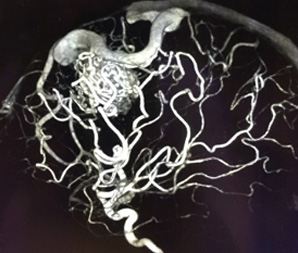

脳動静脈奇形とは、脳にできた異常な血管のかたまり(ナイダス)のことをいいます。通常、脳を栄養する血液は、動脈→毛細血管→静脈の順に流れ、毛細血管から脳へ栄養や酸素を送っています。これに対して、脳動静脈奇形は脳内の動脈と静脈が血管のかたまりであるナイダスで直接つながっており、この中を大量の血液が勢いよく流れています。

2 血管内治療

- ナイダスの中を段階的に液体状の塞栓物質で固めていく方法です。

- 侵襲の低い治療法ですが、血管内治療のみでは完全な治療とならないことが一般的です。

- そのため開頭手術や定位放射線治療を組み合わせて治療を行います。